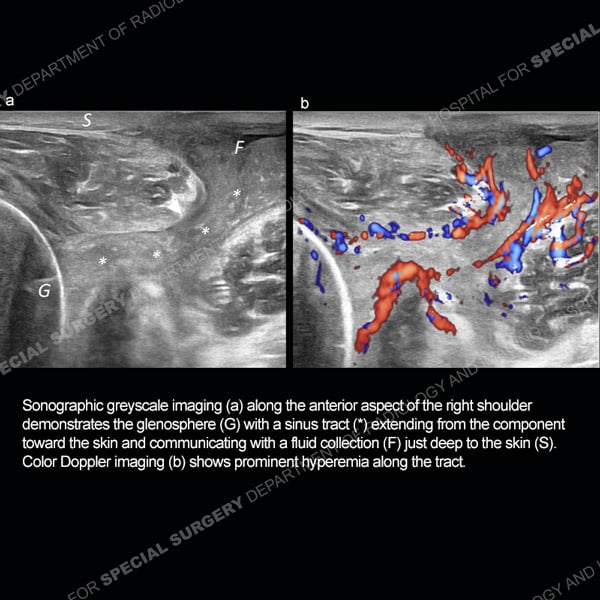

![]() |

Featured Ultrasound of the Month CaseCase 186: 64-year-old woman with new left ring finger soft tissue swelling. |